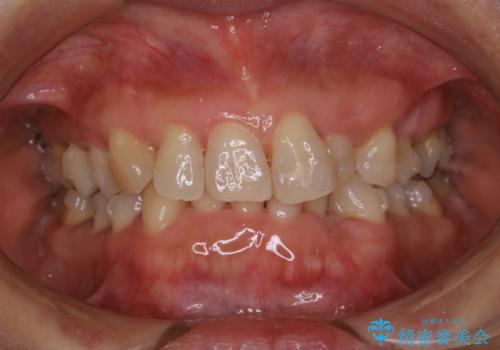

- 上下の歯のがたつきと、噛み合わせが深いことを気にされてご相談にいらした方です。噛み合わせに参加していない歯を抜歯してインビザラインにて治療を行いました。

一般的に噛み合わせの深い方へのインビザライン治療は適応が難しいとされていますが、今回は噛む力を上手にコントロールできたことと、内側に入り込んでいた前歯の角度を調整したことで下の歯がしっかり見えるようになりました。短期間で劇的に見た目が改善し、大変喜んでいただけました。